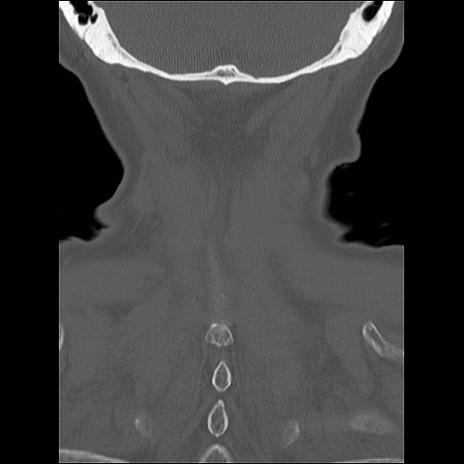

症例48 頚椎CT(冠状断像)

頚椎CT